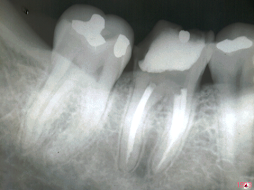

ENDO-OCLUSÃO

A ENDODONTIA PODE FRACASSAR SE A OCLUSÃO TIVER AJUSTADA

PELO DESGASTE APRESENTADO DA PARA IMAGINAR O QUE VAI ACONTECER!!!

SERÁ?

DOR!!!!!!!!!!!!!!!!!

É DA ENDO?

TINHA QUE DAR NISTO!!!!

E AGORA?